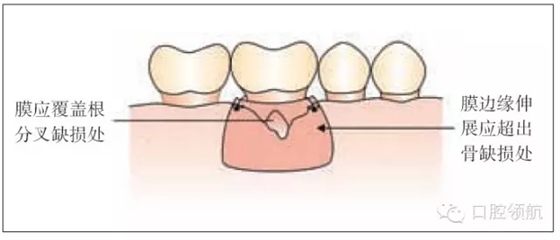

圖26.3 引導(dǎo)組織再生術(shù):膜的放置

·修剪膜使它大小既能覆蓋缺損同時輕輕延伸超過它的邊緣(圖26.3)。